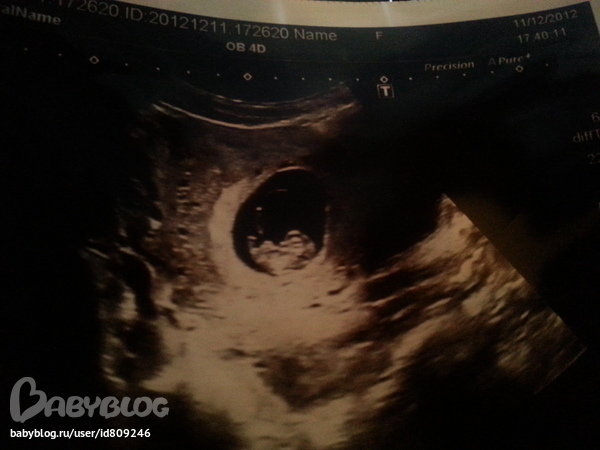

10 недель 5 дней)

Результаты: УЗИ, КТГ, доплера, скринингаДля сравнения УЗИ 8недель 5 дней и 10недель 5 дней) за 2 недельки подросли значительно))

Через 10 дней месячные не пришли - а на УЗИ можно было уже увидеть 3х недельное плодное яйцо)

В 6 недель вставала на учет - отправили на УЗИ, чтобы подтвердить беременность и увидеть сердцебиение)

в 8,5 у меня появились одномоментные коричневые выделения и меня снова отпрвили на УЗИ, благо сказали что риска нет и всё хорошо))

и вот сегодня - первый скрининг))